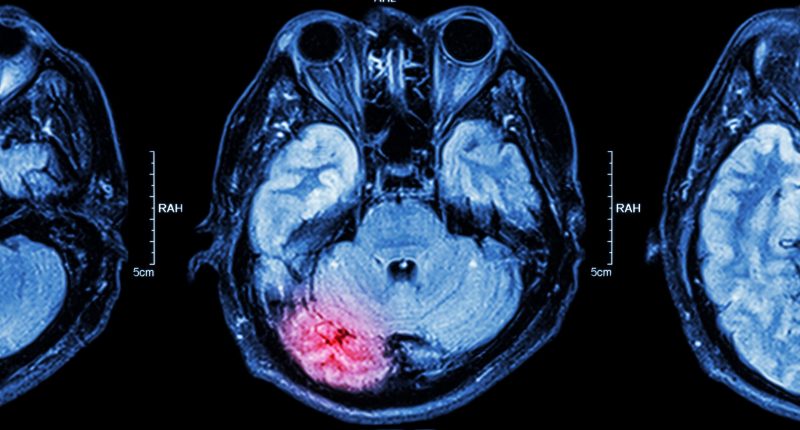

This was confirmed through MRI imaging conducted at the university, which confirmed statistically significant neuroprotection (p = 0.043) for NYR-BI03.

Chair of the Scientific Advisory Board (SAB) and UNSW Scientia Professor Gary Housley said these results were significant. “This study provides strong evidence that Nyrada’s NYR-BI03 drug protected the brain following severe TBI.”

“This was determined using a new MRI approach for quantifying brain tissue integrity.”